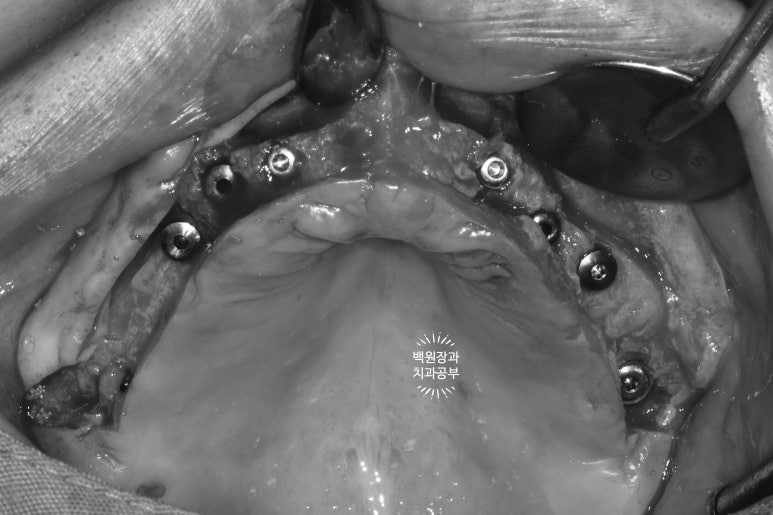

가장 먼저 잇몸뼈의 두께를 확인해야합니다.

CT가 틀릴리 없습니다... 상당히 얇은 잇몸뼈를 관찰할 수 있습니다.

많은 치과에서 절개 없는 임플란트 수술을 한다고 홍보하고 있으나, 이렇게 extreme 하게 많은 뼈이식을 하는 케이스들은 잇몸 절개가 당연히 필수입니다.

수술 시 충분한 절개가 이루어져야 효과적인 잇몸뼈 이식이 가능하고, 임플란트를 좌우 대칭으로 심어드릴 수 있습니다. 고려사항이 상당히 많은 전체임플란트이니만큼, 가능하면 네비게이션 임플란트 수술이 가능한 곳에서 치료 받기를 권해드립니다.

왼쪽 위 잇몸뼈가 상당히 얇음을 역시나 확인할 수 있었습니다.

폭이 약 2-3mm 정도로.. 직경 3.5mm 임플란트를 심을 수 없을 것만 같은 곳이었죠.

이론적으로 3.5mm 임플란트를 심으려면 약 7.5mm 폭의 잇몸뼈를 만들어내야하니 참 곤란한 상황입니다.

오른쪽 위는 그래도 조금 나았던 것으로 기억...

상악동 뼈이식술도 넉넉히 많이 해드려야 했기 때문에, 앞서 언급했던 것처럼 충분한 잇몸 거상이 필요한 상태였습니다. 좋은 시야는 좋은 수술 결과를 만들어내는데 큰 도움을 줍니다.

잇몸뼈가 너무 얇다보니, 임플란트를 위치시키면 이렇게 임플란트의 일부가 드러날 수 밖에 없었고, 이제 어렵디 어려운 잇몸뼈이식이 기다리고 있는 상황..